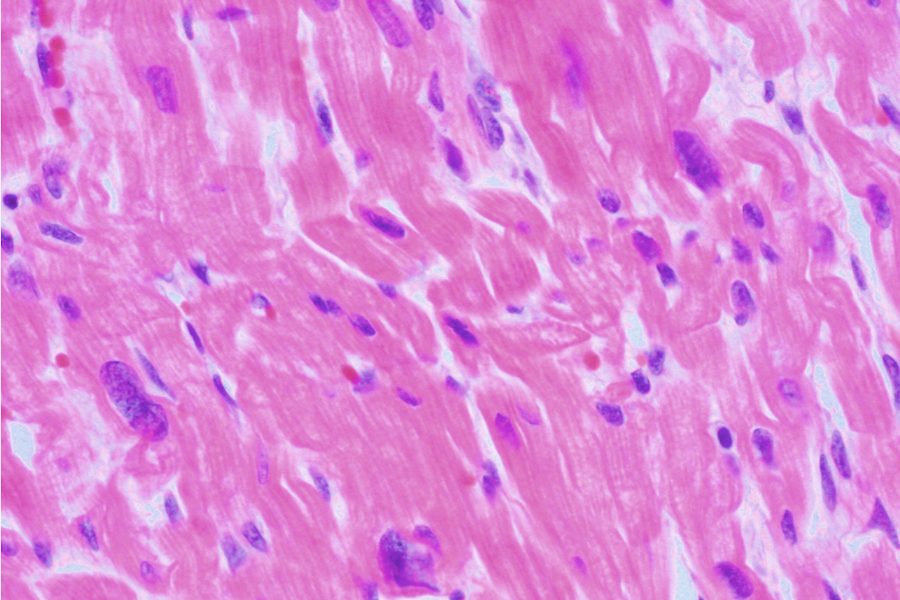

histologische Bilder

adultes Myokard adultes Myokard

hypertensive Herzkrankheit hypertensive Herzkrankheit

hypertrophe Kardiomyopathie hypertrophe Kardiomyopathie

kardiale Amyloidose kardiale Amyloidose

kardiale Hämochromatose kardiale Hämochromatose

Glykogen-Speicherkrankheit Glykogen-Speicherkrankheit

Pathology Residency and Fellowship Program, Brown University, Access 23. October 2022

Elliott P, McKenna WJ (2004) Lancet 363:1881-1891

Internet Pathology Laboratory , University of Utah, Access 23. October 2022

Thoracic Pathology, Cardiac Hemochromatosis, Access 23.October 2022